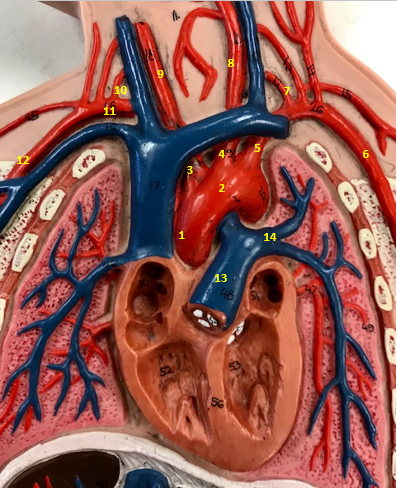

Aorta

Name #2

Brings blood out of left ventricle

Function of aorta

Brachiocephalic artery

Name #3

Supplies oxygenated blood to right arm shoulder neck and head

Function of brachiocephalic artery

Left common carotid artery

Name #4

Supplies oxygenated blood to left neck and head

Function of left common carotid artery

Left subclavian artery

Name #5

Supplies oxygenated blood to left arm shoulder

Function of left subclavian artery

Left axillery artery

Name #6

supplies blood to left armpit and upper limb

Function left axillary artery (6)

Left vertebral artery

Name #7

Supplies blood to brain and spinal cord

Function of left vertebral artery (7)

Left common carotid artery

Name #8

Supplies blood to left neck and head

Function of left common carotid artery (8)

Right common carotid artery

Name #9

Supplies oxygenated blood to right neck and head

Function of right common carotid artery (9)

Right vertebral artery

Name #10

Supplies blood to brain and spinal cord

Function of right vertebral artery (10)

Right subclavian artery

Name #11

Supplies blood to right arm and shoulder

Function of right subclavian artery

Right axillery artery

Name #12

Supplies blood to right armpit and upper limb

Function of right axillery artery (12)

Pulmonary trunk

Name #13

Bring blood out of right ventricle to lungs

Function of pulmonary trunk (13)

Left pulmonary artery

Name #14

Bring blood to left lung

Function of left pulmonary artery (14)